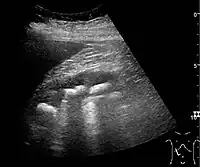

Complex cysts can have membranes dividing the fluid-filled center with internal echoes, calcifications or irregular thickened walls. The complex cyst can be further evaluated with Doppler US, and for Bosniak classification and follow-up of complex cysts, either contrast-enhanced ultrasound (CEUS) or contrast CT is used (Figure 6). The Bosniak classification is divided into four groups going from I, corresponding to a simple cyst, to IV, corresponding to a cyst with solid parts and an 85–100% risk of malignancy.[1] In polycystic kidney disease, multiple cysts of varying size in close contact with each other are seen filling virtually the entire renal region. In advanced stages of this disease, the kidneys are enlarged with a lack of corticomedullary differentiation (Figure 7).[1]